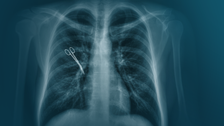

Tausende OP-Behandlungsfehler pro Jahr

Mehrere Tausend Behandlungsfehler mit teils lebenslangen Folgeschäden sind 2024 in Deutschland festgestellt worden. Das geht aus einem Bericht des Medizinischen Dienstes hervor.